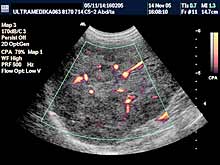

Posebni pregledi:

- Mogu biti nastavljeni nakon standardnog pregleda ako

zato postoje indikacije, ili

- postoje razlozi koji indikuju odmah

poseban pregled!

- Fokalne promene jetre, pankreasa i ostalih parenhimatoznih organa (3D

Sono CT procena i procena vaskularizacije sa Broad band-CD i PD i 3D

CPA modom).